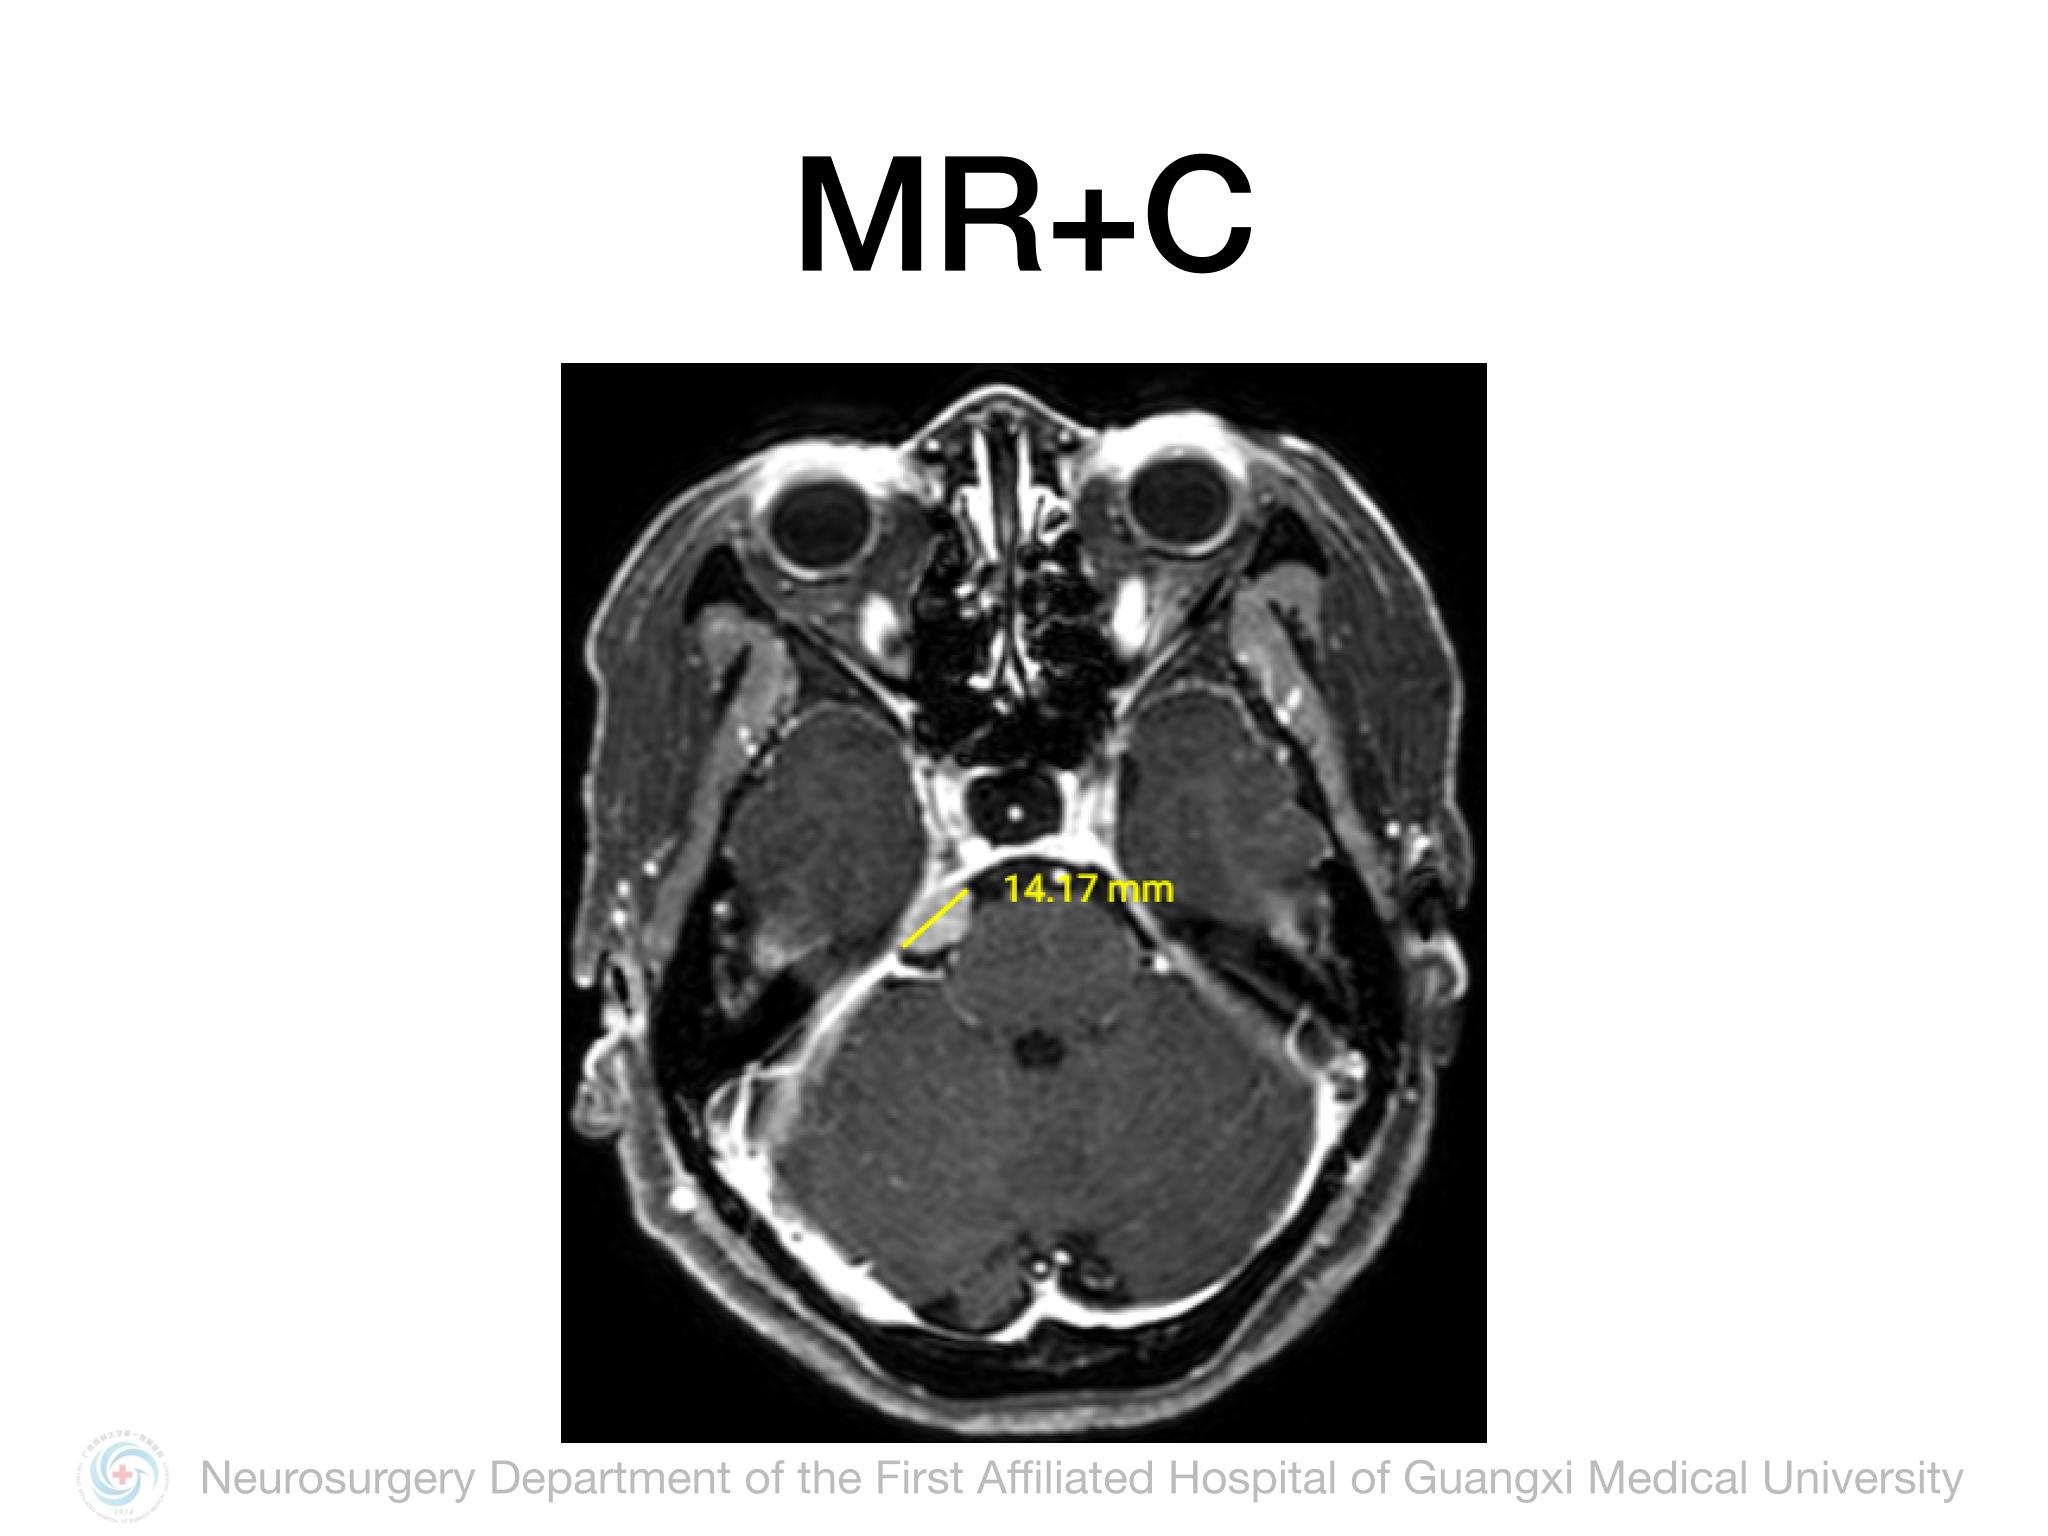

Meckel’s cave(MC)由多层硬膜围绕三叉神经半月结构成,通过三叉神经门与后颅窝蛛网膜下腔相通,起源于MC的脑膜瘤并不常见,文献报道约占所有颅内脑膜瘤的1%。Samii教授报道将MC脑膜瘤分4型,I型:局限于MC;II型:MC脑膜瘤向中颅窝扩展或海绵窦浸润;III型:MC脑膜瘤向CPA区扩展;IV型:MC脑膜瘤向中后颅窝均有扩展。本例属于I型,局限于MC,因此首选颞下经天幕入路,结扎岩上窦,显露部分岩尖,必要时硬膜下磨除岩尖。术中需注意颞叶及Labbe静脉壁保护,避免损伤岩静脉,尽可能全切肿瘤及基底。本例术中见肿瘤基底位于MC外侧壁及顶壁,主体位于MC,向后下推挤三叉神经,向后颅窝有部分延伸,但与脑干无黏连,向三叉神经内侧进入MC内侧空间,充分显露MC后将肿瘤及其基底全切,周围神经血管保护良好,术后无新发神经功能障碍,疗效满意。